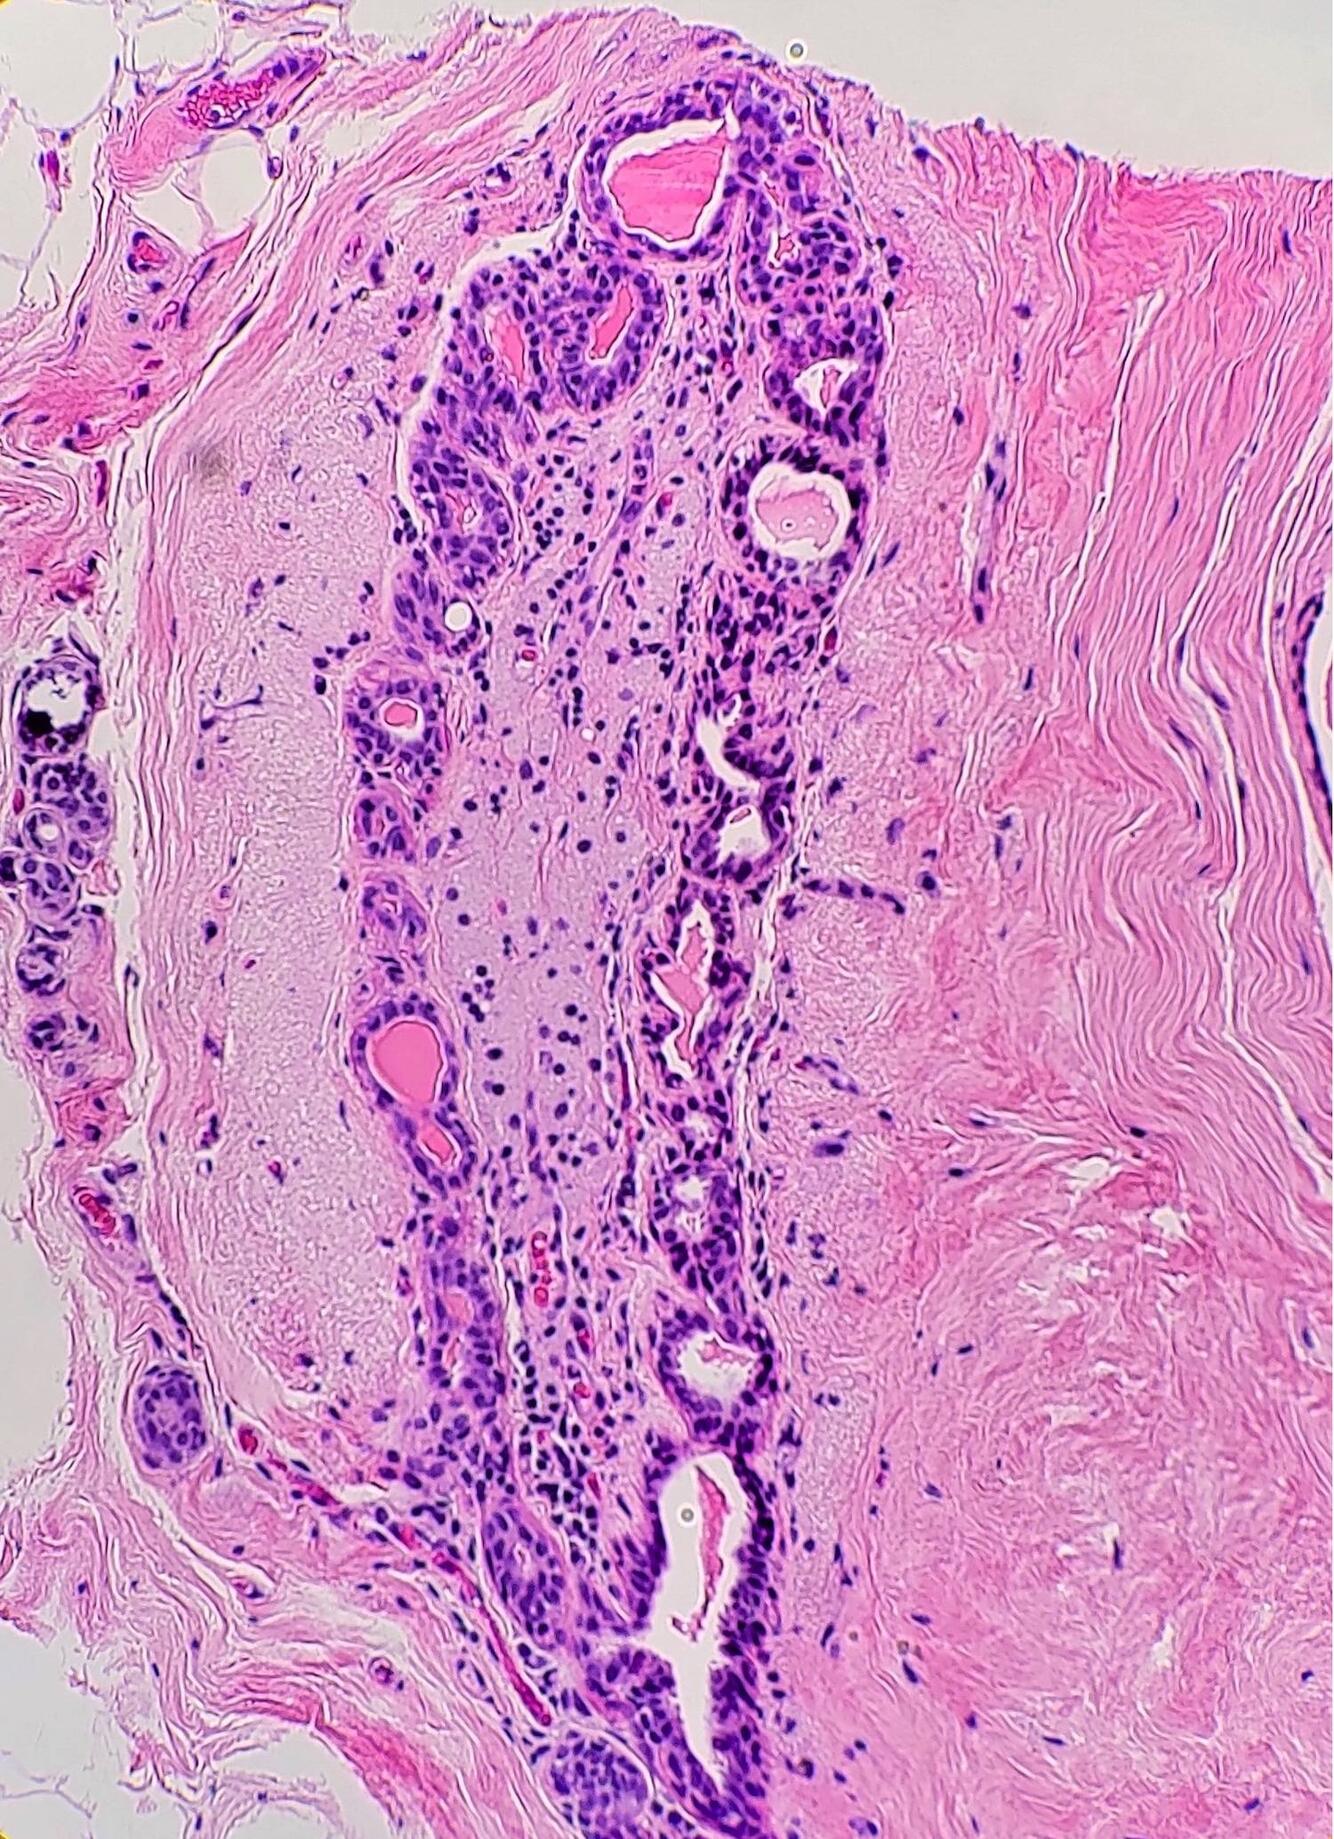

Taken from a male patient

Gynecomastia

Contains fibrous stroma and branching ducts with terminal ductules, but extremely few (if any) acini. In early stages, there is a loose periductal stroma with a mixed chronic inflammatory infiltrate, extensive epithelial hyperplasia, and tapering tufts (pyramid-shaped micropapillae). In later stages, there is fibrosis and hyalinization of periductal stroma and epithelial atrophy.

Here, early stage gynecomastia is shown.

Benign lesion of the male breast, often bilateral. Caused by androgen/estrogen imbalance. Physiologic in children, but often pathogenic in adults. May be seen normally during puberty, or in those taking dopaminergic medications, hormone therapy, those with Klinefelter syndrome, cirrhosis, or obesity.

No associated risk of malignancy.